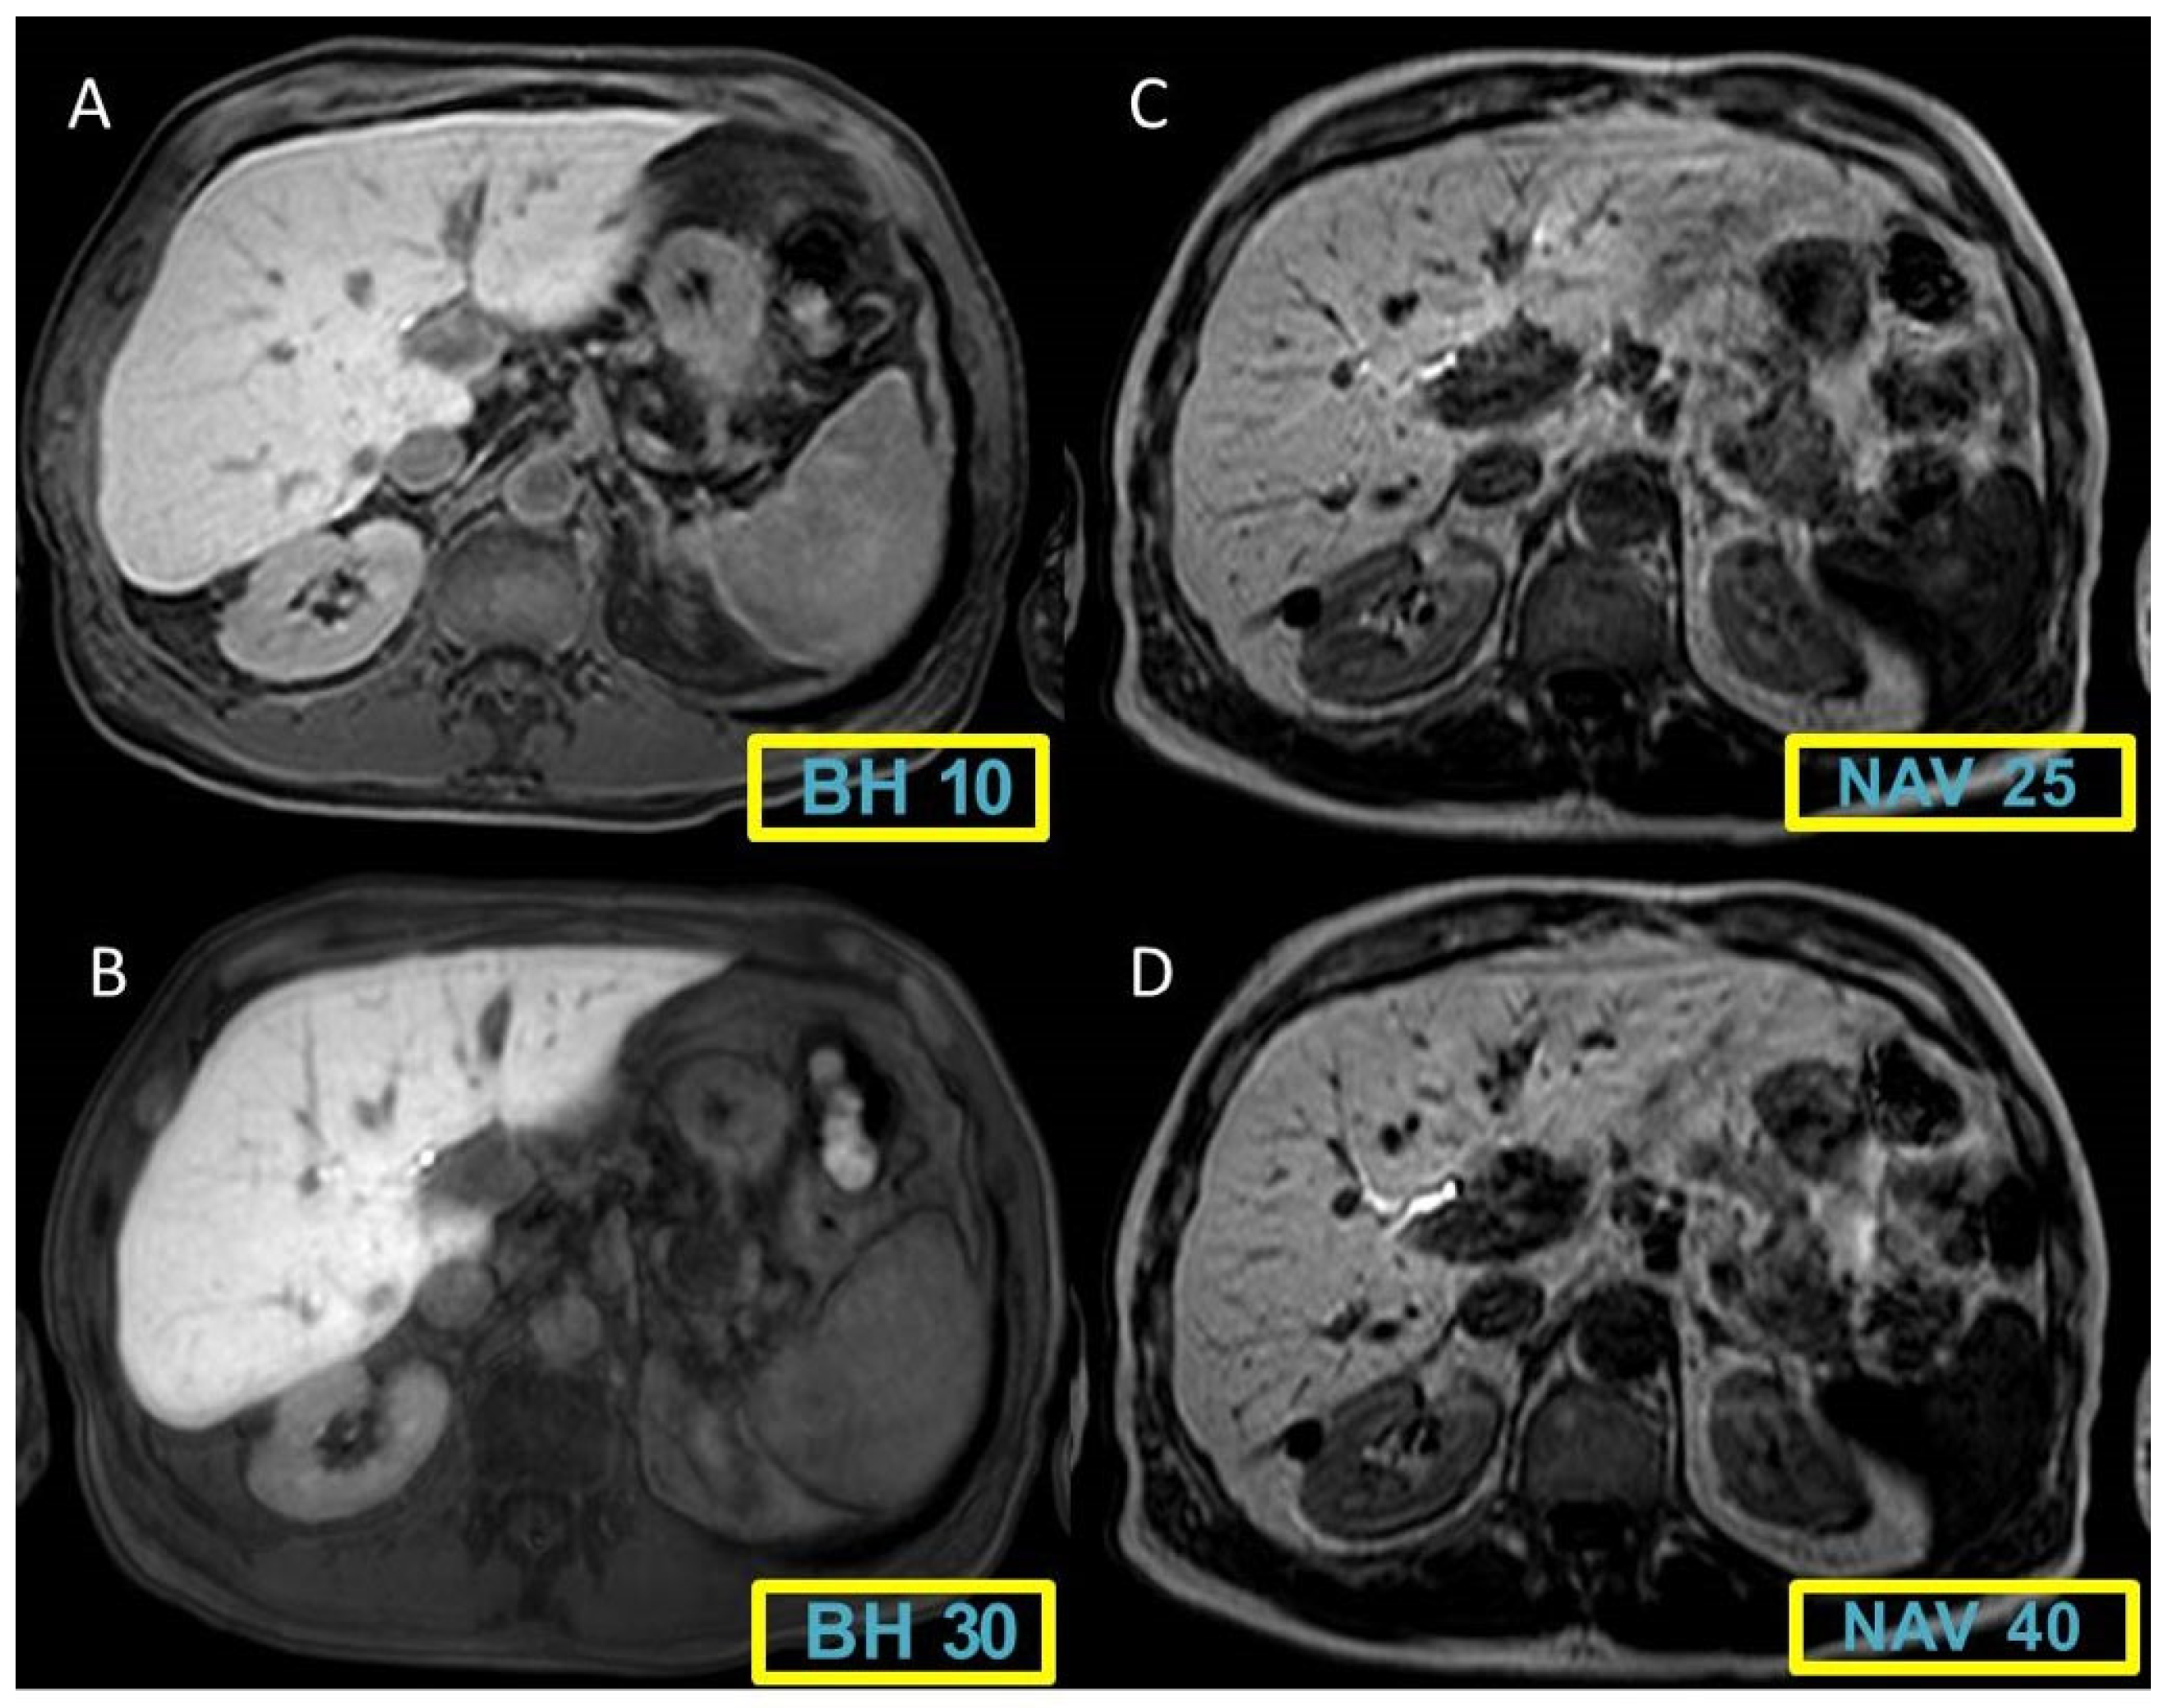

Figure 1 and Figure 2 display representative cases to visually illustrate these findings, providing a clear view of how different MRI sequences affect the CNR between liver and spleen tissues.

Figure 2. A 56 years-old patient with liver cirrhosis and malignant lesion (arrows). The contrast between the images is growing in Breath-hold (BH) sequences (A-B) and even greater in those with free breathing navigated sequences (NAV) (C-D).